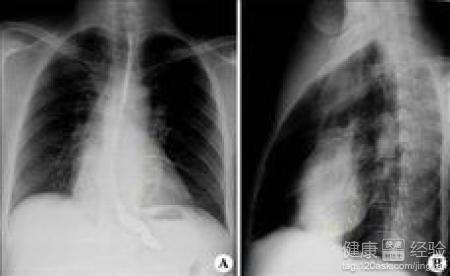

縮窄性心包炎的治療

縮窄性心包炎常繼發於急性心包炎之後,但是也有其他疾病引起,發病原因比較復雜,在這裡我只跟大家聊聊該病的治療方法。該病的治療其實也不復雜,雖說是有其他疾病發展而來,病情惡化比較嚴重,但是進行一些臨床治療還是可以治愈的。